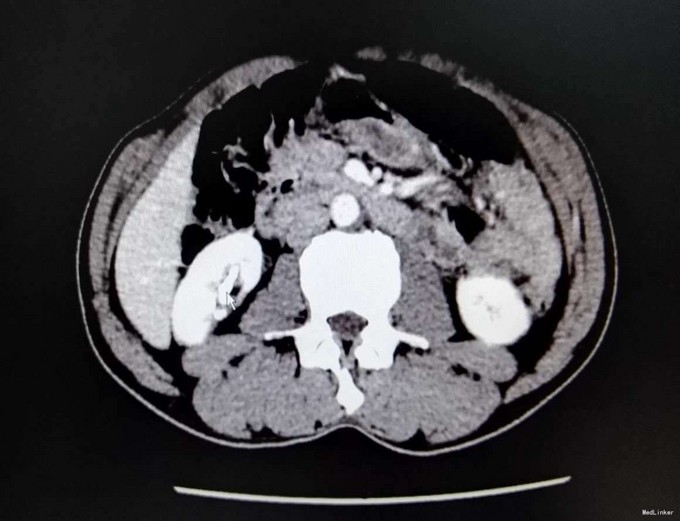

1、患者中年男性,慢性病程,既往有泌尿系结石史 2、患者2年前无明显诱因出现右侧腰部疼痛,疼痛呈放射状,阵发性,无恶心、呕吐,无尿频、尿急,尿痛,无排尿困难,无血尿、脓尿,我院门诊就诊,查KUB提示:右肾多发结石

3、查体:右肾区叩击痛(+),右侧肋脊点、肋腰点压痛(+),余查体未见明显异常 4、辅助检查:我院KUB提示:右肾多发结石,CTU平扫+增强:1、右肾多发结石,右肾下极局限性萎缩2、双肾多发囊张,3、肝多发囊肿

5、肾结石(右肾多发结石) 6、住院后完善相关检查,双肾CTU平扫+增强如上述,诊断为右肾多发结石,行右侧输尿管逆行置管术,手术顺利,术后恢复较好,顺利出院